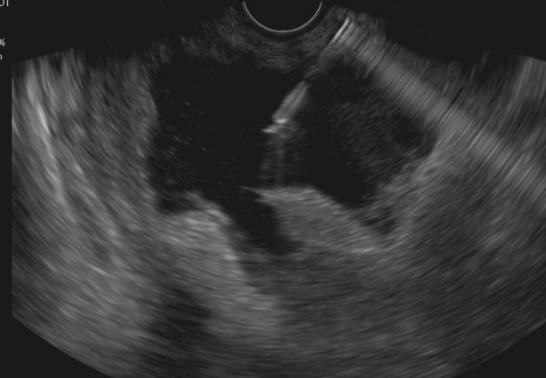

手术当天,超声内镜下,坏死腔清晰呈现。孙家琛成功将穿刺针经胃壁精准置入巨大的坏死包裹腔内,抽出约20毫升褐色坏死液送检。这一步,不仅验证了路径的正确,也为后续抗感染治疗提供了关键的病原学依据。

超声穿刺针精准置入腔内